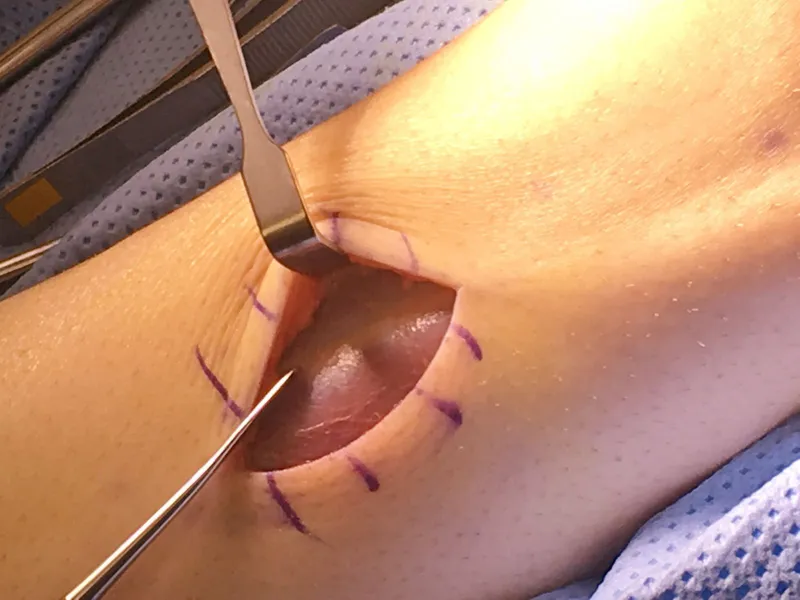

Intra-operative image of open fasciiotomy for chronic exertional compartment muscle syndrome where the bulging muscle belly can seen at the center of the image from build up of pressure within the compartment.

The following is the fascial covering over a muscle compartment. The condition occurs when pressure within this compartment builds up after an injury or can also occur after excercise from the inability of the muscle to decompress naturally. This leads to pain that is unrelenting and could lead to decreas blood flow and oxygen to muscle tissue causing death of that tissue.

The picture below demonstrates the fascia overlying the tissue being lifted by the forceps at the top of the picture.

Below is demonstrates incision into the compartment exposing the muscle tissue that is a deeper red color where the retractor is to the left of the picture. The opening of the this fascial tissue is vital in releasing pressure in the compartment after injury or from excercise. It also important that this release be extensive as so the fascial tissue does not heal closed allowing build of pressure again.